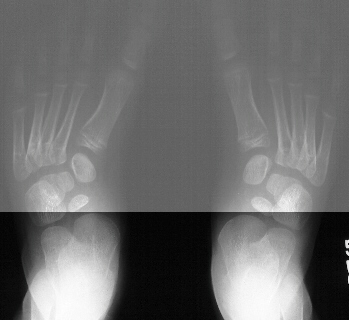

A 2 year old boy was seen for evaluation of intoeing. He had

been previously diagnosed with bilateral metatarsus adductus at

another institution. His prior treatment consisted of serial casting

for eight weeks which began shortly after birth, this was followed

by corrective shoes until 12 months of age. His parents felt that

the metatarsus adductus had improved since birth, however they

still had concerns over the residual deformity. They denied that

their child had any functional problems. There was a positive

maternal family history of "intoeing" which was treated

with a Dennis Browne bar and corrective shoes. Examination revealed

a well-appearing child. He had bilateral mild internal tibial

torsion, however the major component of his intoeing appeared

to be secondary to bilateral metatarsus adductus deformities which

were supple and flexible and they were both able to be corrected

to neutral position. The patient returned for follow-up at the

age of 5 years and 1 month. His mother stated that he still had

residual intoeing, and he appeared more clumsy with gait than

other children his age. She was concerned that his metatarsus

adductus had not corrected, and she wanted to know if anything

more could be done. The patient still had not had any functional

problems, nor had he any shoe wear problems. Examination revealed

bilateral flexible metatarsus adductus deformities. There was

no evidence of any skin breakdown or callous formation. He did

have a noticeable valgus right heel with a less obvious left heel

valgus deformity. His subtalar motion was maintained.